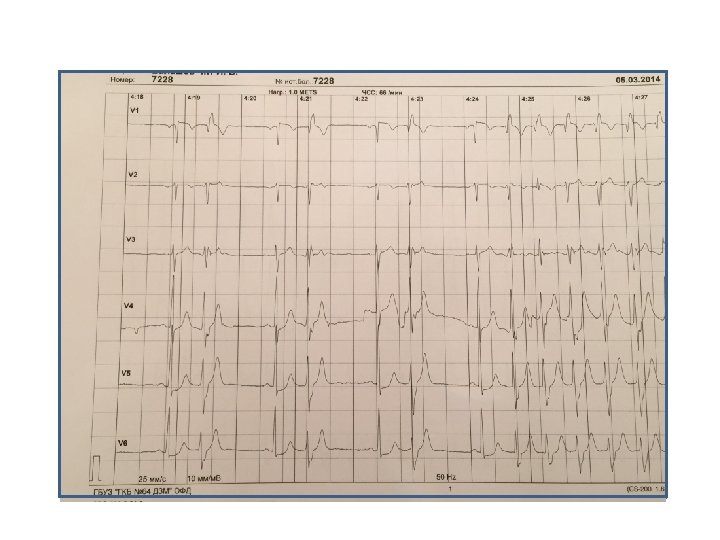

Пациент Б. , 58 лет Направление: диагностика ИБС

Пациент Б. , 58 лет Направление: диагностика ИБС